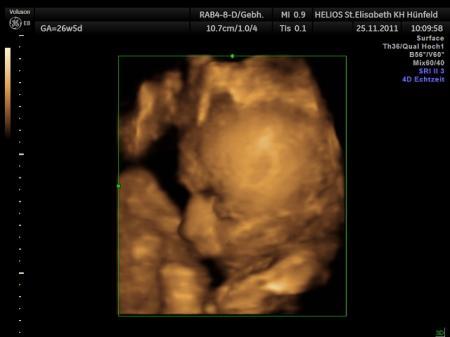

Bild zu

Angelbaby1202